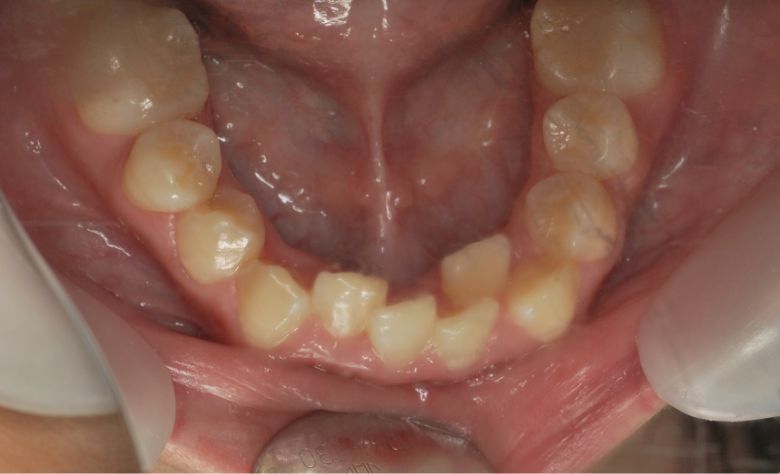

上下顎ともに犬歯が唇側に大きく突出しており、歯列弓が狭小なため、

他院では上下左右4本の便宜抜歯を前提とした矯正治療を提案されていました。

下の前歯が3本、強く重なり合って生えており、歯並びの乱れが目立つ

精密検査の結果、当院では抜歯を行わず、歯列弓の拡大によってスペースを確保し、非抜歯での矯正治療を選択しました。歯列の叢生(ガタガタ)は解消され、機能的かつ審美的に優れた咬合が得られました。